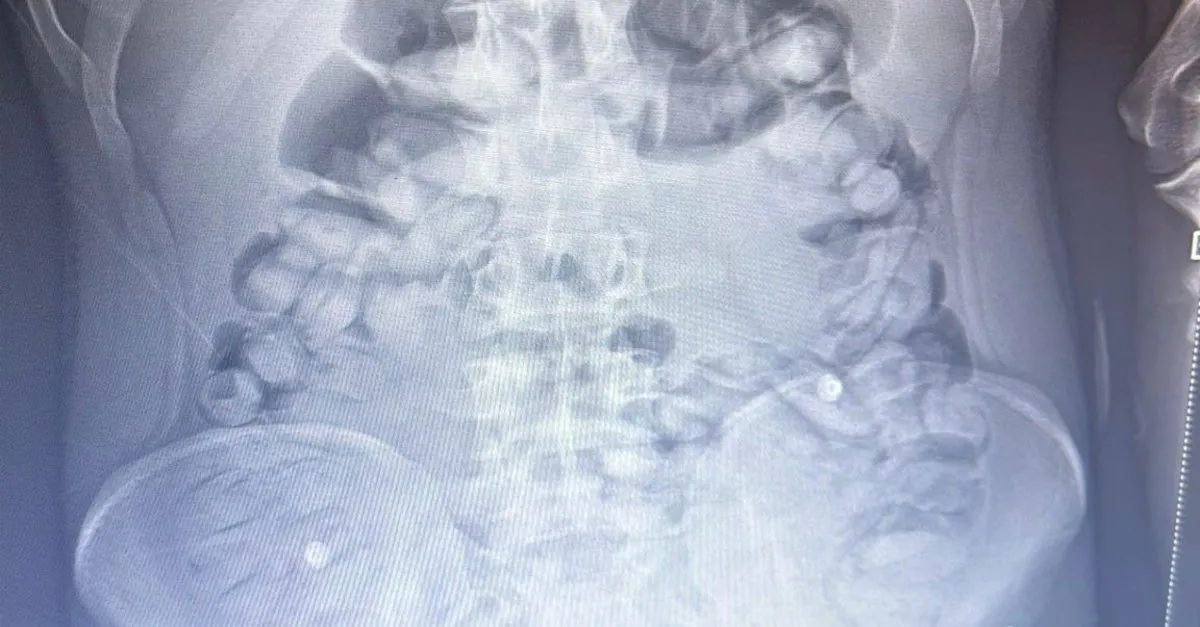

"Uyuşturucu madde ticareti ve sevkiyatına yönelik yapılan çalışmalar neticesinde 13.11.2023 tarihinde tespit edilen yolcu otobüsünde durumunlarından şüphelenilenerek uyuşturucu madde yutmuş olabileceği değerlendirilen ve İlimiz Şehir Hastanesinde iç beden muayenesi yaptırılan S.A. (2006 doğumlu) isimli şahıstan toplam 1 kilo 134 gram Afyon Sakızı maddesi ele geçirilmiş, konuyla ilgili adli mercilere sevk edilen şahıs tutuklanarak cezaevine teslim edilmiştir.